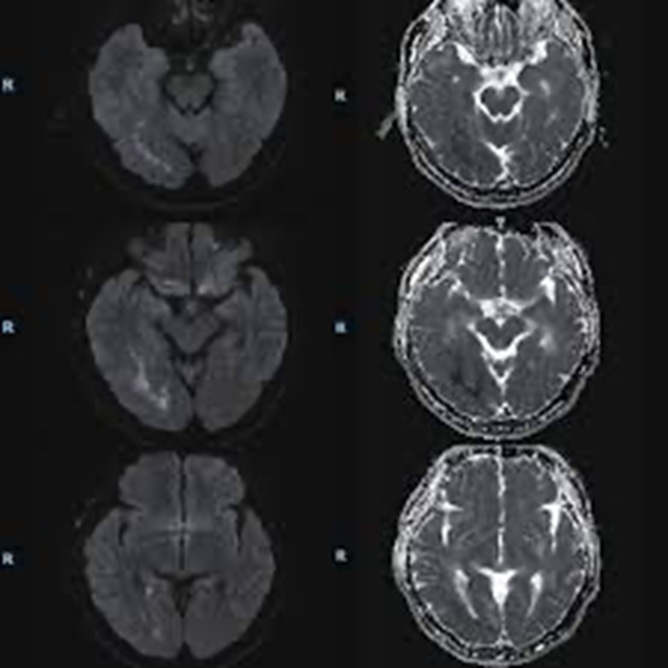

При МРТ головного мозга выявлены изменения, соответствующие острому ишемическому инсульту.

Острые ишемические изменения в коре правой височной и затылочной долей